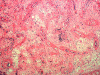

Histopathology: Panel B is taken at the periphery of the tumor where a well circumscribed margin is demonstrated. The tumor has rich vascularity and a hypocellular stroma. However, increased stromal cellularity is present in some areas.  Hyalinized blood vessels and a sclerotic to edematous stroma are well demonstrated in Panel C. Also present are a few lymphocytes clustering around blood vessels. The sclerotic stroma with edema and sparse lymphocytic infiltration is demonstrated in Panels D and E. The bland cytologic features are shown in Panel F.

Macroscopically, AMFBs range from 0.5 cm to 14 cm in greatest dimension with the majority of them between 2-8 cm. The lesions are well-circumscribed, round, ovoid, or lobulated masses with a soft to rubbery consistency. The cut surface varies from gray-pink to yellowish brown to tan and is of homogeneous texture with focal myxoid areas. Microscopically, the margin is well delineated and non-infiltrative. A complete or partial fibrous pseudocapsule of varying thickness may be present. Some tumors are bordered in part by mature adipose tissue or smooth muscle. The tumor is characterized by rich vascularization in a background of collagenous to edematous stroma with alternating hyper- and hypocellular regions 3. The stromal background is edematous rather than myxoid. The nature of the background is supported by negative staining for Alcian blue stain.

The stromal cells possess a bland, oval or elongated nuclei and either scanty, amphophilic cytoplasm with ill-defined margins or eosinophilic, tapered cytoplasm with better delineated cell borders. Intranuclear inclusions and longitudinal nuclear grooves are common in the spindle cells. Epithelioid mesenchymal cells with globoid eosinophilic cytoplasm and a single nucleus or occasional multiple, round nuclei may be present. Mitotic figures are characteristically rare or absent. The cellularity is quite variable and is somewhat related to the vascularity. In most cases, the spindled and epitheloid cells proliferate in a haphazard arrangement. In the more cellular cases, spindled cells form loosely organizing fascicles. Tumor cells may aggregate or form masses around blood vessels and those that are close to blood vessels may have a myoepithelial appearance. The vascular component of the tumor consists of small to medium-sized, rounded, curvilinear, non-branching, and thin-walled vessels. Perivascular fibrosis or sclerosis is a feature detected to some degree in all cases 11.  Mature adipocytes can be sparsely scattered within the neoplasm and, in rare cases, adipose cells predominate; such tumors have been classified as the “lipomatous” variant of angiomyofibroblastoma 8 by some investigators. Strong and diffuse immunoreactivity for both desmin and vimentin is demonstrated in practically all cases. Only a minority of cells in some cases show positive immunoreactivity for either smooth muscle actin or pan-muscle actin 1, 12, 13, 14 , 15. Tumor cells are negative for S-100 protein, cytokeratin, collagen type IV, CD 68 and myoglobin 16. The few cases examined ultrastructurally have shown fibroblastic features in most cells, with a minority showing myofibroblastic differentiation 1, 12, 14.